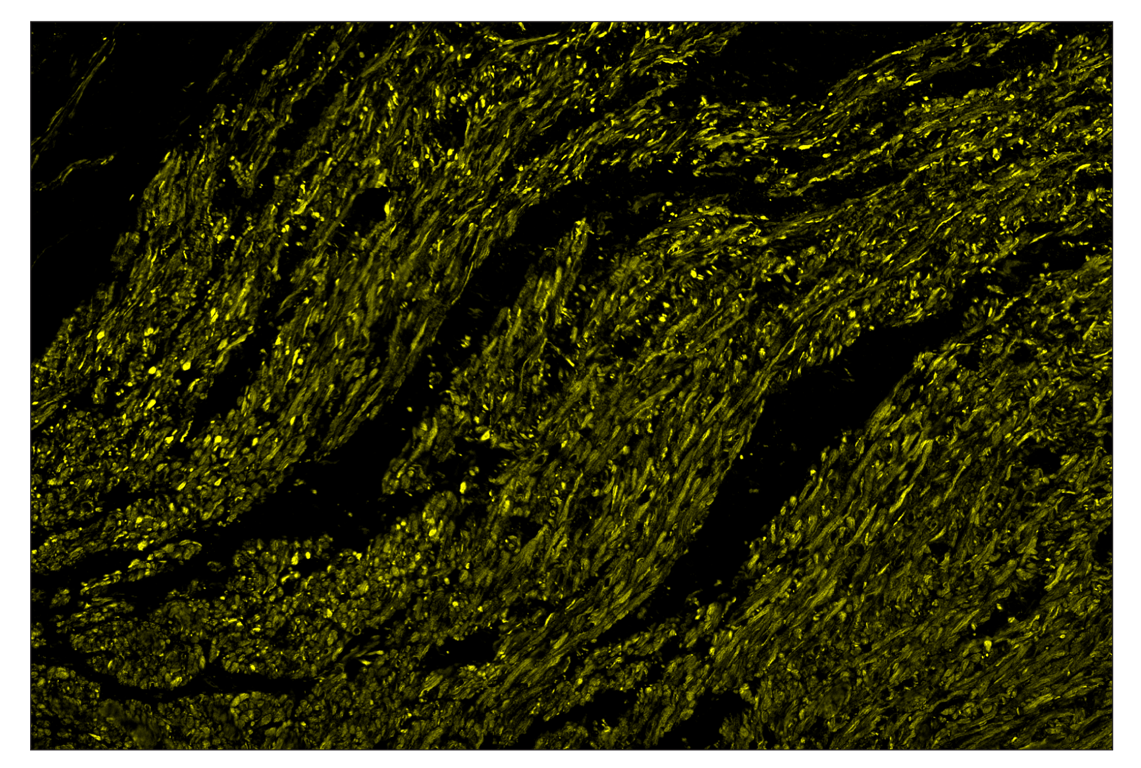

SignalStar™ multiplex immunohistochemical analysis of paraffin-embedded human colorectal adenocarcinoma using OX40L (D6K7R) & CO-0087-594 SignalStar™ Oligo-Antibody Pair #58323 (yellow). All fluorophores have been assigned a pseudocolor, as indicated. Staining was performed on the BOND RX autostainer by Leica Biosystems.

Immunohistochemistry Image 3: OX40L (D6K7R) & CO-0087-488 SignalStar<sup>™</sup> Oligo-Antibody Pair